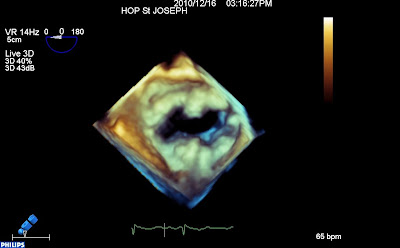

Valve ouverte :

Valve fermée (enfin presque, car le P3 et son cordage prolabent)

On distingue toujours le prolapsus de P3 (cette fois à droite de l’écran, sur cette vue « chirurgicale » de la mitrale : auricule à droite, aorte en haut, commissure postérieure à droite de l’écran). Mais on prend la mesure de l’énorme calcification de l’anneau mitrale, quasi circonférentielle, qui ne paraissait pas franchement évidente en 2D…